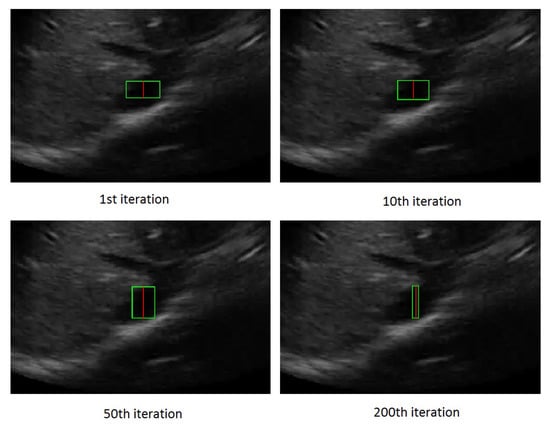

Figure 4 shows the rectangle evolution versus number of iterations for the IVC image as in Figure 2. By comparison of Figure 2 and Figure 4, one can see the active rectangle algorithm not only converges faster but also more accurately estimates the AP-diameter than the active ellipse algorithm.

Figure 4.

The rectangle evolution versus number of iterations.